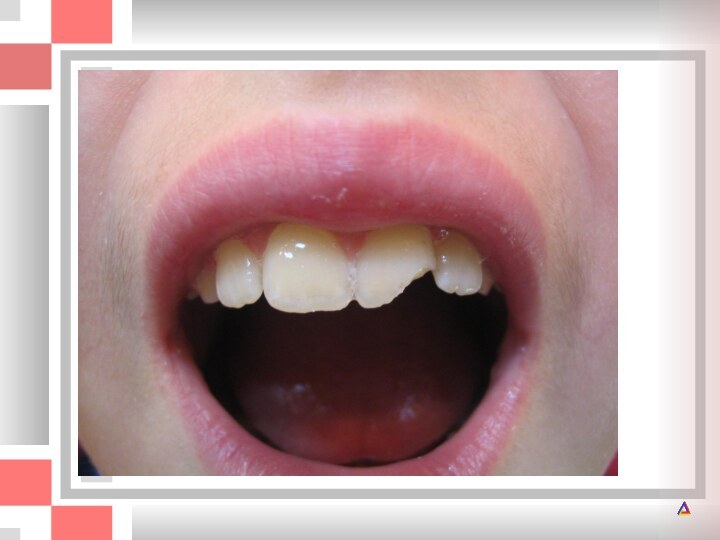

А и Б - перелом коронок верхних центральных резцов с обнажением

резцов с обнажением пульпы. Вся язычная поверхность эмали правого

центрального резца отсутствует. Произведена ампутация пульпы; В - проведена реставрация зубов композитом без препарирования. Дополнительной ретенции удалось достичь за счет заполнения пульпарной камеры пломбировочным материалом. Штифты не использовались.